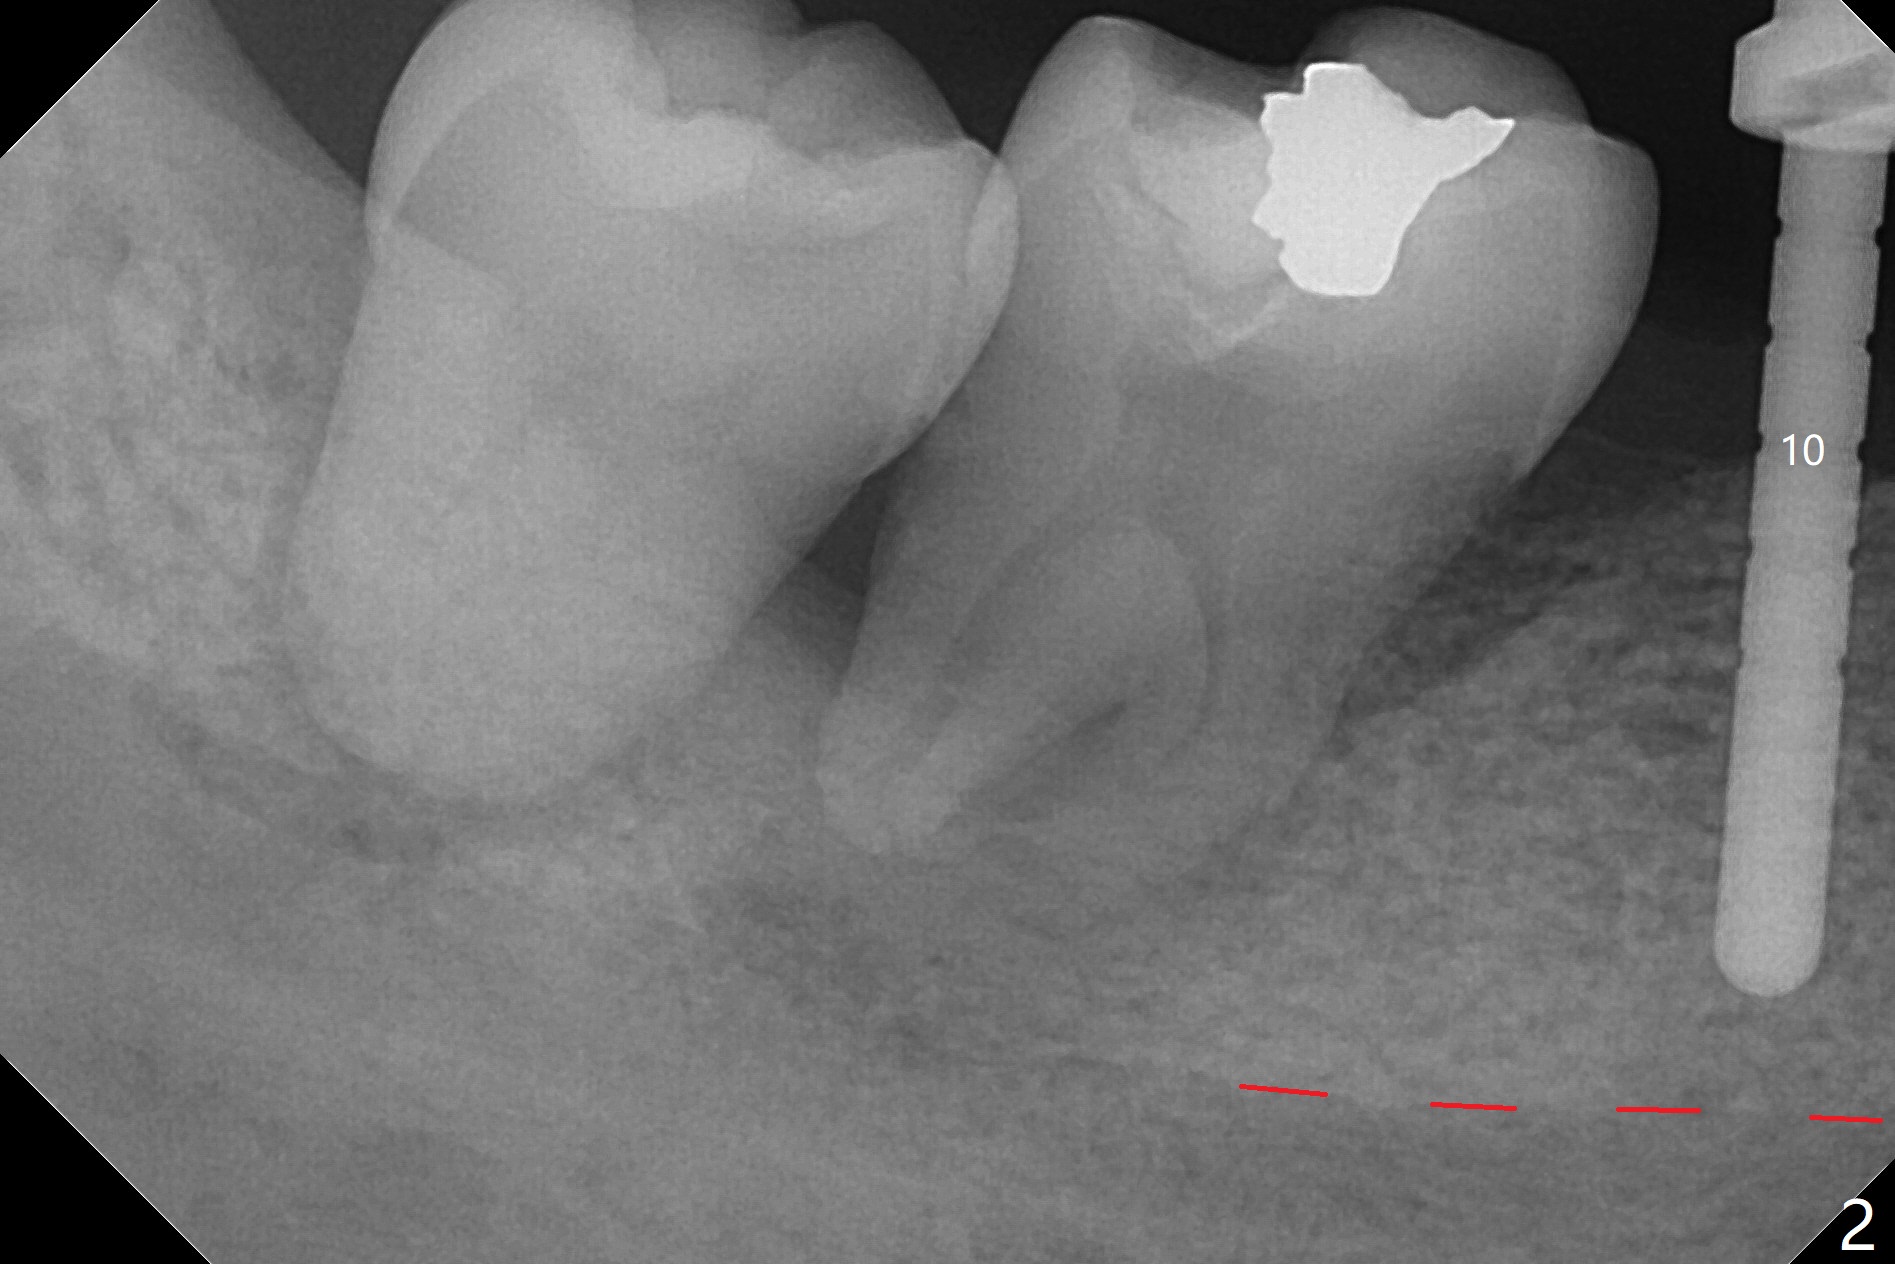

The ridge at #30 is not so narrow (Fig.1). Initial depth is 10 mm with 2 mm from the Inferior Alveolar Canal (Fig.2,3 red dashed line). A 4.5x10 mm implant is placed with > 50 Ncm; a 6.2x5(3) mm healing abutment placed (Fig.4). The implant is stable and seems to be ready for impression 3 months postop (Fig.5). CT taken 5 months post cementation shows that the implant could be placed more lingually (Fig.6 (coronal section; B: buccal)). Periradicular radiolucency at #31 (Fig.7 *) is continuous with the Inferior Alveolar neurovascular bundle (N). After extraction, care should be taken to remove granulation tissue. The tooth #32 will be extracted simultaneously because of severe bone loss.